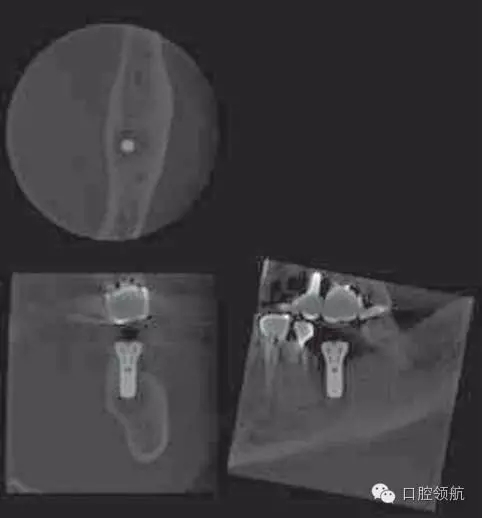

術(shù)后第18天,進行CBCT的確認(圖5),種植體周圍發(fā)現(xiàn)不透過影像,而且種植體有松動,因此在浸潤麻醉下拔除(圖6~圖8)。

圖5 術(shù)后18天CBCT的影像。